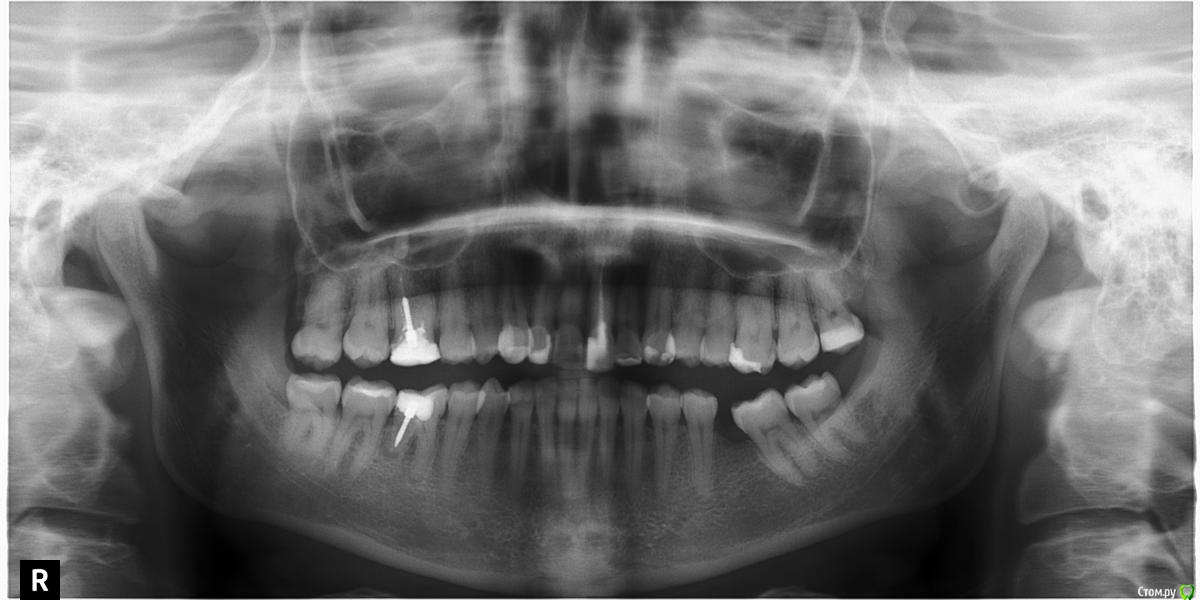

Валерьич Опубликовано 24 сентября, 2016 Поделиться Опубликовано 24 сентября, 2016 Добрый день. Снимок моей супруги ходившей на прием сегодня. Одно мнение хорошо,а много- лучше.Пояснение- передние сверху в винирах, которым 13 лет. Пора менять, это факт. Те что справа коренные под пломбами темные, верхний как бы амортизирует. Врач(или рвач?)- сказал что виниры надо убирать, зубы прятать под коронки. Насчитали 300 тысяч за 6 коронок . В общем мы в шоке от этой суммы, вроде в бюджетную клинику ходила и тут такое.Прошу многоуважаемое сообщество посмотреть снимок и дать план лечения. посоветовать с чего начинать если и вправду о таких суммах идет речь.Жена коронки вперед не хочет однозначно... 2 Ссылка на комментарий

red_butler Опубликовано 25 сентября, 2016 Поделиться Опубликовано 25 сентября, 2016 Врач(или рвач?) к чему клеить ярлыки??? Жена коронки вперед не хочет однозначно... хотеть не хотеть, уже не важно, если не будет коронок на зубах, то будут на коронки на имплантах.По плану... профессиональная гигиена и затем1. удалять зубы мудрости и возможно 4.62. перелечивать 1.63. ревизия корневого канала 2.14. создания места для протезирования в области 3.6 (брекеты)5. имплантация в позицию 3.6 и возможно 4.66. протезирование вкладками и коронками 1.6 2.1, импланта/тов, фронт керамические коронки или виниры. А главное увидели мой вопрос не про лечение а стоимость. я тоже увидел... Насчитали 300 тысяч за 6 коронок . В общем мы в шоке от этой суммы, вроде в бюджетную клинику ходила и тут такое. Прошу многоуважаемое сообщество посмотреть снимок и дать план лечения. посоветовать с чего начинать если и вправду о таких суммах идет речь. 1 1 Ссылка на комментарий

DmitrySH Опубликовано 27 сентября, 2016 Поделиться Опубликовано 27 сентября, 2016 Маленькое уточнение.Тканей у зуба 21 фактически нет, соответственно коронка. Можете ее обозвать полным виниром, можно керамической реставрацией. Ссылка на комментарий